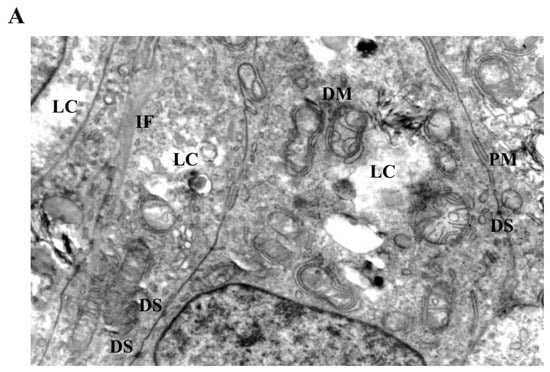

Figure 4.

Ultrastructural changes in Ishikawa spheroids following low-dose LiCl exposure (24 h). (A) Control spheroids display preserved mitochondrial morphology with intact cristae, organized cytoplasm, and normal plasma membrane integrity. (B) Treatment with 1 mM LiCl reveals early mitochondrial alterations, including focal cristae irregularities and double-membrane (DM) isolation structures, accompanied by mild cytoplasmic vacuolization and localized intermediate filament (IF) accumulation. Abbreviations: M, mitochondrion; N, nucleus; G, Golgi apparatus; PM, plasma membrane; DM, double membrane; IF, intermediate filament; V, vacuole; Scale bar: 500 nm.

3.4. Ultrastructural Mitochondrial Alterations in LiCl-Treated Spheroids

Ultrastructural analysis by transmission electron microscopy revealed distinct LiCl-induced alterations affecting mitochondrial morphology and intermediate filament organization in 3D Ishikawa endometrial cancer spheroids (Figure 4, Figure 5 and Figure 6). Control spheroids displayed preserved cellular architecture, including mitochondria with intact outer and inner membranes, well-organized cristae, and homogeneous matrix density. The cytoplasm exhibited an organized intermediate filament network, intact plasma membranes, and preserved intercellular junctions (Figure 4A).

Exposure to low-dose LiCl (1 mM) was associated with early mitochondrial alterations, including focal cristae irregularities and the appearance of double-membrane-like structures morphologically resembling isolation membranes in close proximity to mitochondria (Figure 4B). These changes occurred without widespread cytoplasmic lysis, plasma membrane disruption, or global structural disorganization. At 72 h, low-dose LiCl treatment was characterized by an increased frequency of double-membrane structures and subtle mitochondrial matrix alterations (Figure 5B), consistent with an early-stage mitochondrial stress response.